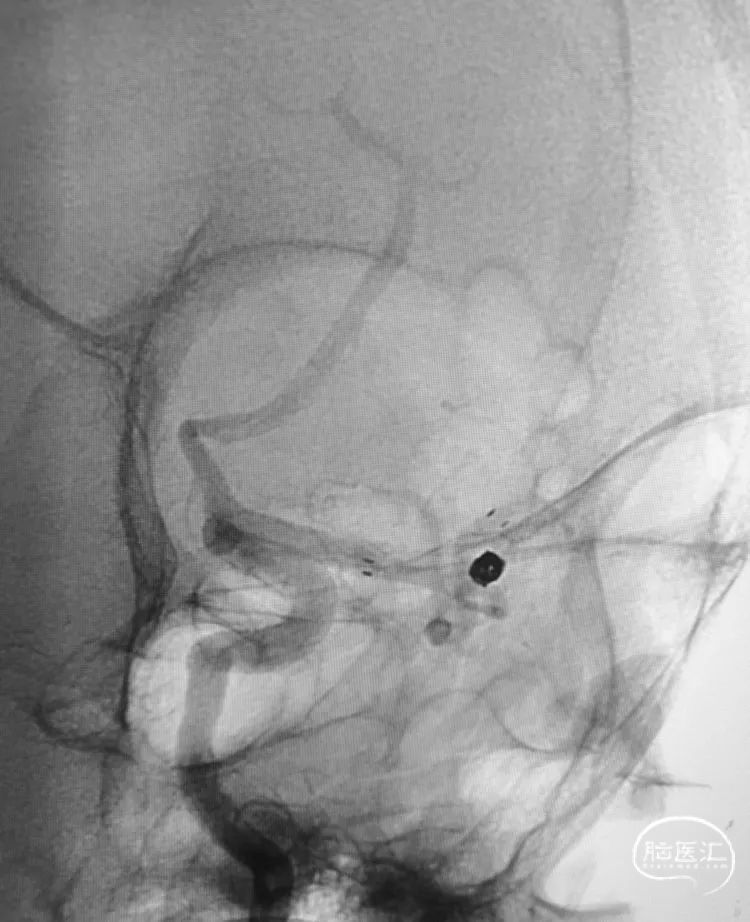

这个弓型不好弄!果断使用6F 70长鞘。

颈总动脉更尴尬,是块硬骨头。

多角度显示动脉瘤,中动脉分三干,瘤体和上干关系密切,宽颈,准备支架!Atlas非常适合这样的血管。